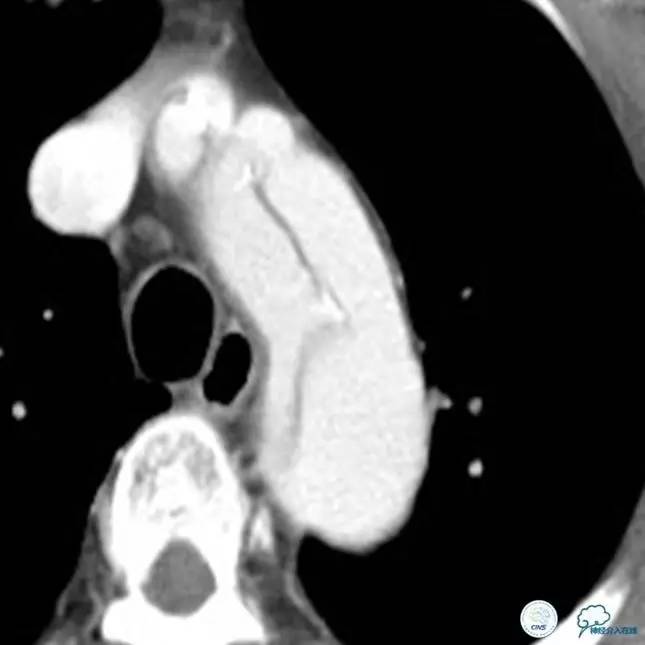

▼主动脉全程CT

诊断:

主动脉夹层 DeBakey Ⅰ型

中间诊断:

主动脉夹层 De Bakey Ⅰ型